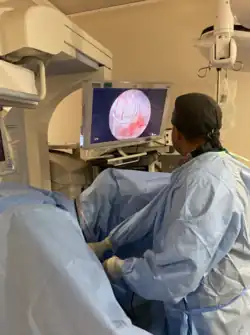

Aufgaben der Urologie sind Wissenschaft, Lehre, Diagnose und Behandlung von Krankheiten der Harnorgane und der männlichen Geschlechtsorgane.[4][5] Dazu gehören konservative und operative endourologische, laparoskopische und offene urologische Therapien und auch Steinzertrümmerungen oder Laserbehandlungen zum Schneiden und Verdampfen unerwünschten Gewebes.

Die Einführung neuer Untersuchungsmethoden wie Sonografie, Computertomografie und nuklearmedizinische Untersuchungen führte zu einer erheblichen Verbesserung im Erkennen und Therapieren urologischer Erkrankungen. Die Entdeckung des Penicillins und die Weiterentwicklung der Antibiotika reduzieren die Infektionsrate und damit die Sterblichkeit drastisch. Neue Operationsverfahren wie die radikale Prostatektomie oder die radikale Zystektomie (Entfernung der Harnblase) mit Blasenersatz werden entwickelt. Die erste erfolgreiche Nierentransplantation wird 1956 durchgeführt. Der Fortschritt auf dem Gebiet der Endoskopie ermöglicht die Entwicklung der transurethralen Resektion zur Behandlung von gutartigen Prostatavergrößerungen und des Harnblasenkrebses. Harnsteine können heute im Körper zertrümmert werden (→ Lithotripsie). Neue kleinste Endoskope ermöglichen die Inspektion nicht nur der Harnblase (Zystoskopie), sondern auch von Niere und Harnleiter (Ureteroskopie). Die Möglichkeit der Untersuchung und Behandlung über optische Systeme führte zum jüngeren Teilgebiet der Endourologie. Die Chemotherapie und die Strahlentherapie verbessern die Behandlungsmöglichkeiten von Tumorerkrankungen. Schließlich hält die Laparoskopie in den 1990er Jahren Einzug in die Urologie, die erste laparoskopische Nephrektomie wurde 1991 und die erste laparoskopische Prostatektomie wurde 1992 durchgeführt.[69]

Die laparoskopische Technik wurde durch die Verwendung eines Operationsroboters (Da-Vinci-Operationssystem) weiterentwickelt, welcher vor allem in der Urologie zum Einsatz kommt. Auch die Spezialisierung schreitet in der Urologie stetig voran. In einer noch jungen urologischen Spezialdisziplin, der Neurourologie, werden alle Störungen des Harn- und Genitaltraktes behandelt, die durch eine Verletzung oder Erkrankung des Nervensystems verursacht wurden. Vor allem Patienten mit einer Querschnittlähmung sind davon betroffen, aber auch Patienten mit Multipler Sklerose, Morbus Parkinson oder nach einem Schlaganfall. Weitere Spezialdisziplinen der Urologie sind die Andrologie (Lehre der Fortpflanzungsfunktionen des Mannes), die Kinderurologie (angeborene Erkrankungen) und die in Deutschland ab 1900[70] vor allem von Walter Stoeckel (Berlin) und Karl Burger (Würzburg) vorangetriebene gynäkologische Urologie[71] bzw. Urogynäkologie (unter anderem Behandlung von Harn- und Stuhlinkontinenz sowie Lageveränderungen der Genitalorgane von Frauen).